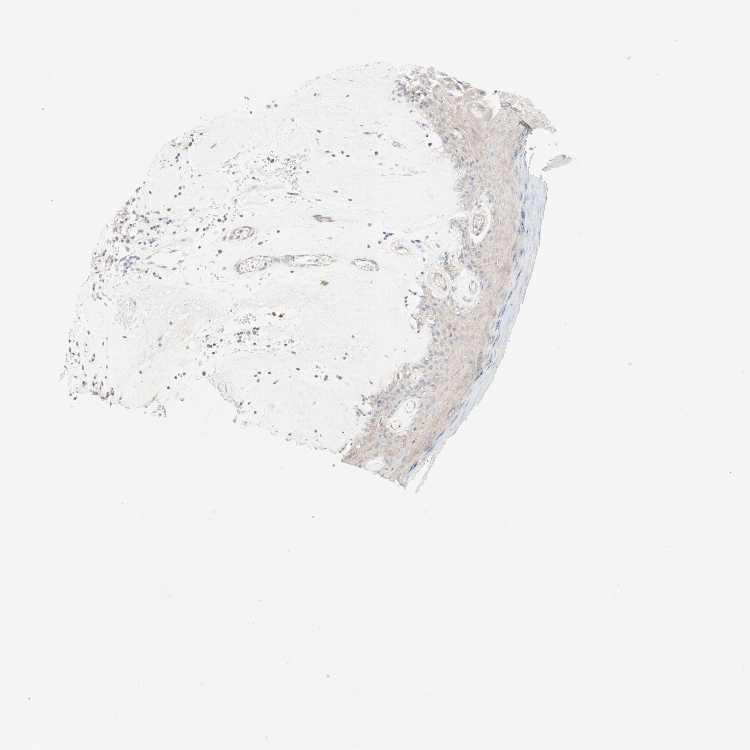

TISSUE PRIMARY DATA SKIN Show tissue menu

SKIN 1 - Antibody stainingi

Antibody staining in the annotated cell types in the current human tissue is reported as not detected, low, medium, or high, based on conventional immunohistochemistry profiling in selected tissues. This score is based on the combination of the staining intensity and fraction of stained cells.

Each image is clickable and will lead to virtual microscopy that enables deeper exploration of all samples and also displays staining intensity scores, fraction scores and subcellular localization as well as patient and tissue information for each sample.

SKIN 2 - Antibody stainingi